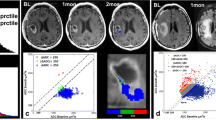

a Postcontrast T1-weighted MR image (inset) showing a recurrent enhancing lesion in a patient with previously treated high grade glioma. MR spectroscopy from the enhancing lesion (red) showing increased Cho/Cr with decrease in the NAA suggestive of recurrent tumor. Spectrum from the contralateral normal appearing white matter showing normal levels of the metabolites (blue). b However, perfusion CT blood volume map showed reduced blood volume in the lesion suggesting predominant treatment effects. Histopathology revealed pure radiation necrosis with no viable tumor cells confirming that Cho/Cr ratio was probably increased due to active demyelination rather than due to tumor

One of the major hurdles in using any of these functional imaging techniques as a follow up tool to quantify treatment response is lack of standardization of image acquisition and post-processing for most of the techniques. Many of these measures can vary depending upon the scanner type and strength used (particularly true for ADC and eigenvalues) [75], type and strength of the tracer/contrast agent and bolus used apart from change in patient’s hemodynamics on follow up visits. Many of these factors significantly limit absolute quantification of these physiologic and metabolic measures. This has been compensated to some degree by using relative values obtained by dividing absolute values from the lesion with absolute values obtained from the normal appearing white or gray matter. Because of these, there is also lack of development of standard values for many of these functional parameters and hence, these measures cannot be implemented across multiple centers. However, recently dynamic contrast enhanced MR imaging has been used to estimate vascular permeability in recurrent glioblastomas treated with cediranib to assess treatment response [76]. Water diffusivity measurements have also been used to assess treatment response and tumor growth patterns in the recent past [9, 77–79]. Most of the discussed functional imaging techniques can potentially be useful for targeting foci of tumor in a heterogeneous mixture of tumor and necrosis for biopsy and radiation planning. Foci of tumor which appear as ‘hot spots’ i.e. usually show high metabolism or perfusion, due to active, mitotic tumor cells in a heterogeneous mixed tumor necrosis lesion may be targeted to increase the yield of a surgical biopsy procedure. Similarly, targeted radiation therapy with a boost to the ‘hot spots’ potentially can increase the effectiveness while limiting neurotoxicity in the future (Fig. 11).

59 year old male, previously treated for a malignant glioma with chemotherapy and radiation, developed radiation necrosis proven with histopathology and remained stable for 4 years. a Follow up imaging showed recurrent enhancing lesion (arrowheads) in the previously stable heterogeneously enhancing radiation necrosis (arrows). DCE T1-MR perfusion parametric maps showed increased (b, c) blood volume and (d, e) Ktrans in the recurrent enhancing lesions (arrowheads) as ‘hot spots’ suggesting recurrent tumor, with in relatively low blood volume and Ktrans stable radiation necrosis region (arrows). These ‘hot spots’ were used for the planning of fractionated re-irradiation. f Radiation therapy isodose lines showing higher dose delivered to the hot spots with relative sparing of the previously stable radiation necrosis region